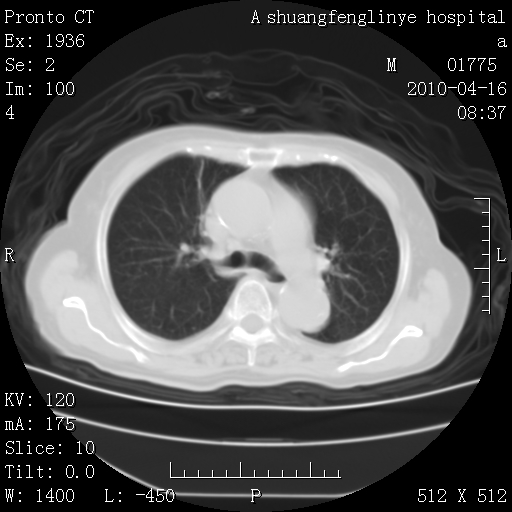

标题: CT25784:咳痰、请会诊!结核? [打印本页]

标题: CT25784:咳痰、请会诊!结核?

考虑左肺上叶增殖灶、纤维灶。

慢支肺气肿,左上陈旧性结核,主动脉冠脉钙化

1)左肺上叶结核(纤维、增殖病灶)。2)冠状动脉及主动脉钙化。

1)左肺上叶结核(纤维、增殖病灶)。2)冠状动脉及主动脉钙化。肺动脉高压